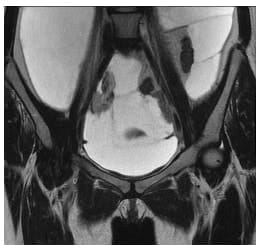

Se realizó una resonancia magnética de abdomen y pelvis que demostró la ocupación de todos los recesos peritoneales con líquido complejo de diferentes captaciones y septos multiloculados, la ocupación del espacio subfrénico derecho debido al desplazamiento tanto del hígado en sentido superior, como de las asas intestinales incluyendo el colon derecho en sentido central y en sentido posterior rechazando el colon descendente. No había compromiso retroperitoneal.

Se encontró además una lesión quística dominante adyacente al pedículo ovárico derecho sin conformarse propiamente una masa ovárica, lo que hizo sospechar el origen en la trompa.

Debido a la presentación clínica y a los resultados de la resonancia, se sospechó un pseudomixoma peritoneal de probable origen apendicular (Figuras 1-3).

Figura 3. Resonancia magnética abdominal en corte coronal T2 con supresión grasa.

Se observa el origen del primer quiste en la trompa de Falopio derecha.